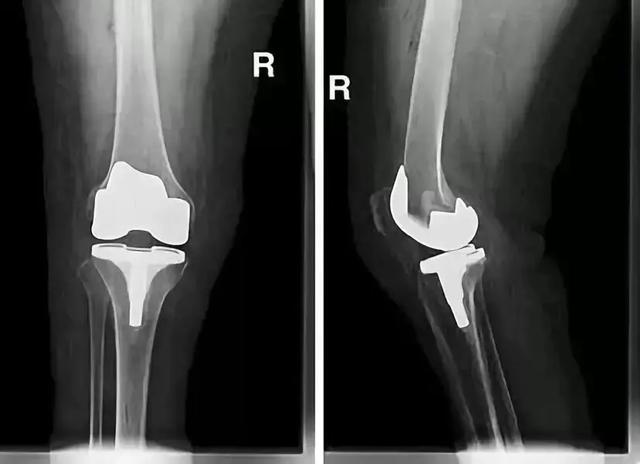

人工关节形成新的关节摩擦面 , 彻底避免了骨头磨骨头 , 也松解了关节僵硬 , 应该说是解除后期骨关节炎患者膝关节疼痛的最有效方法 。

关节置换置换手术

现在的人工关节材料和技术已经非常成熟 , 通常认为55岁以后适合关节置换 , 60到75岁是最佳置换年龄 。 然而 , 是否手术越迟 , 结果就越好呢?我不以为然 。 对每个具体病人而言 , 生理年龄比实际年龄更重要 , 身体好、生理年龄小(虽然实际年龄已达60岁)的病人手术时间确实可适当推迟 。。

随着病人年龄增长 , 心肺功能只会每况愈下 , 如果有手术指征 , 可以考虑适当提早手术 , 这样不仅减少手术风险 , 也使患者可以早日行走锻炼 , 促进心肺功能的康复 。